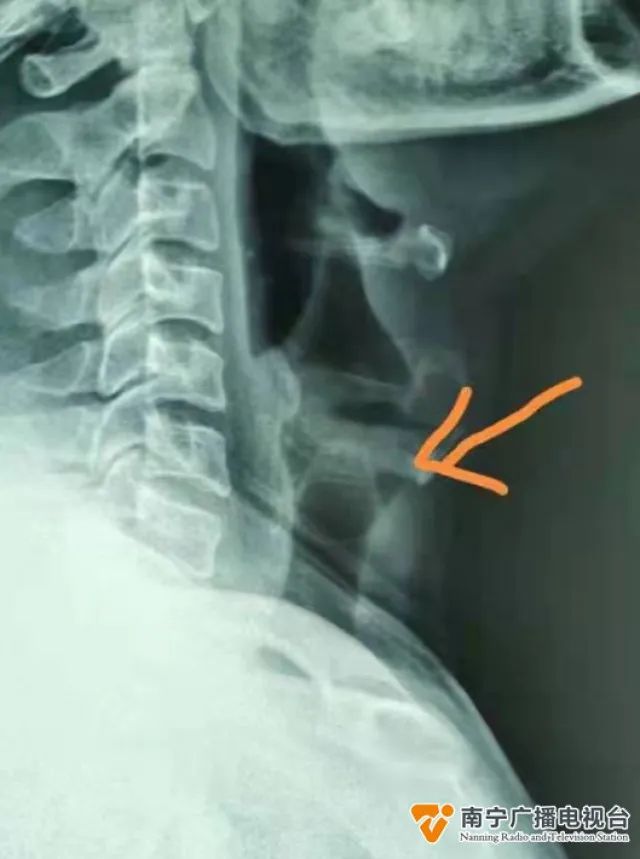

3月25日下午,一名男子在家屬的陪同下急匆匆來(lái)到廣西壯族自治區(qū)民族醫(yī)院就診,稱自己和朋友聚會(huì)喝啤酒時(shí),不小心把酒瓶拉環(huán)一口喝下,造成進(jìn)食進(jìn)水困難......

醫(yī)院耳鼻咽喉科副主任醫(yī)師唐亮說(shuō):“這個(gè)病人是3月25日下午,跟朋友一起喝酒的時(shí)候,喝了一罐帶拉環(huán)的易拉罐啤酒,把拉環(huán)拉開(kāi)的時(shí)候,可能沒(méi)有處理好,就連拉環(huán)一起吞到了喉部,拉環(huán)就直接卡在了咽喉的入口處。

醫(yī)生介紹,這名男子來(lái)到醫(yī)院時(shí),距離吞下異物已經(jīng)有2個(gè)多小時(shí)。經(jīng)過(guò)檢查發(fā)現(xiàn),酒瓶的拉環(huán)已經(jīng)從食道滑到了氣管入口處,期間,男子還出現(xiàn)了呼吸困難的跡象。

唐亮說(shuō):“在放射科的時(shí)候,這個(gè)病人躺下來(lái)做CT時(shí),已經(jīng)出現(xiàn)了窒息的情況,我們趕緊安排去急診科吸氧做了一些急救。在手術(shù)期間,我們給病人做了一個(gè)全身麻醉,用氣管異物鉗把卡在氣管的異物取出,解除了病人危險(xiǎn)的情況!